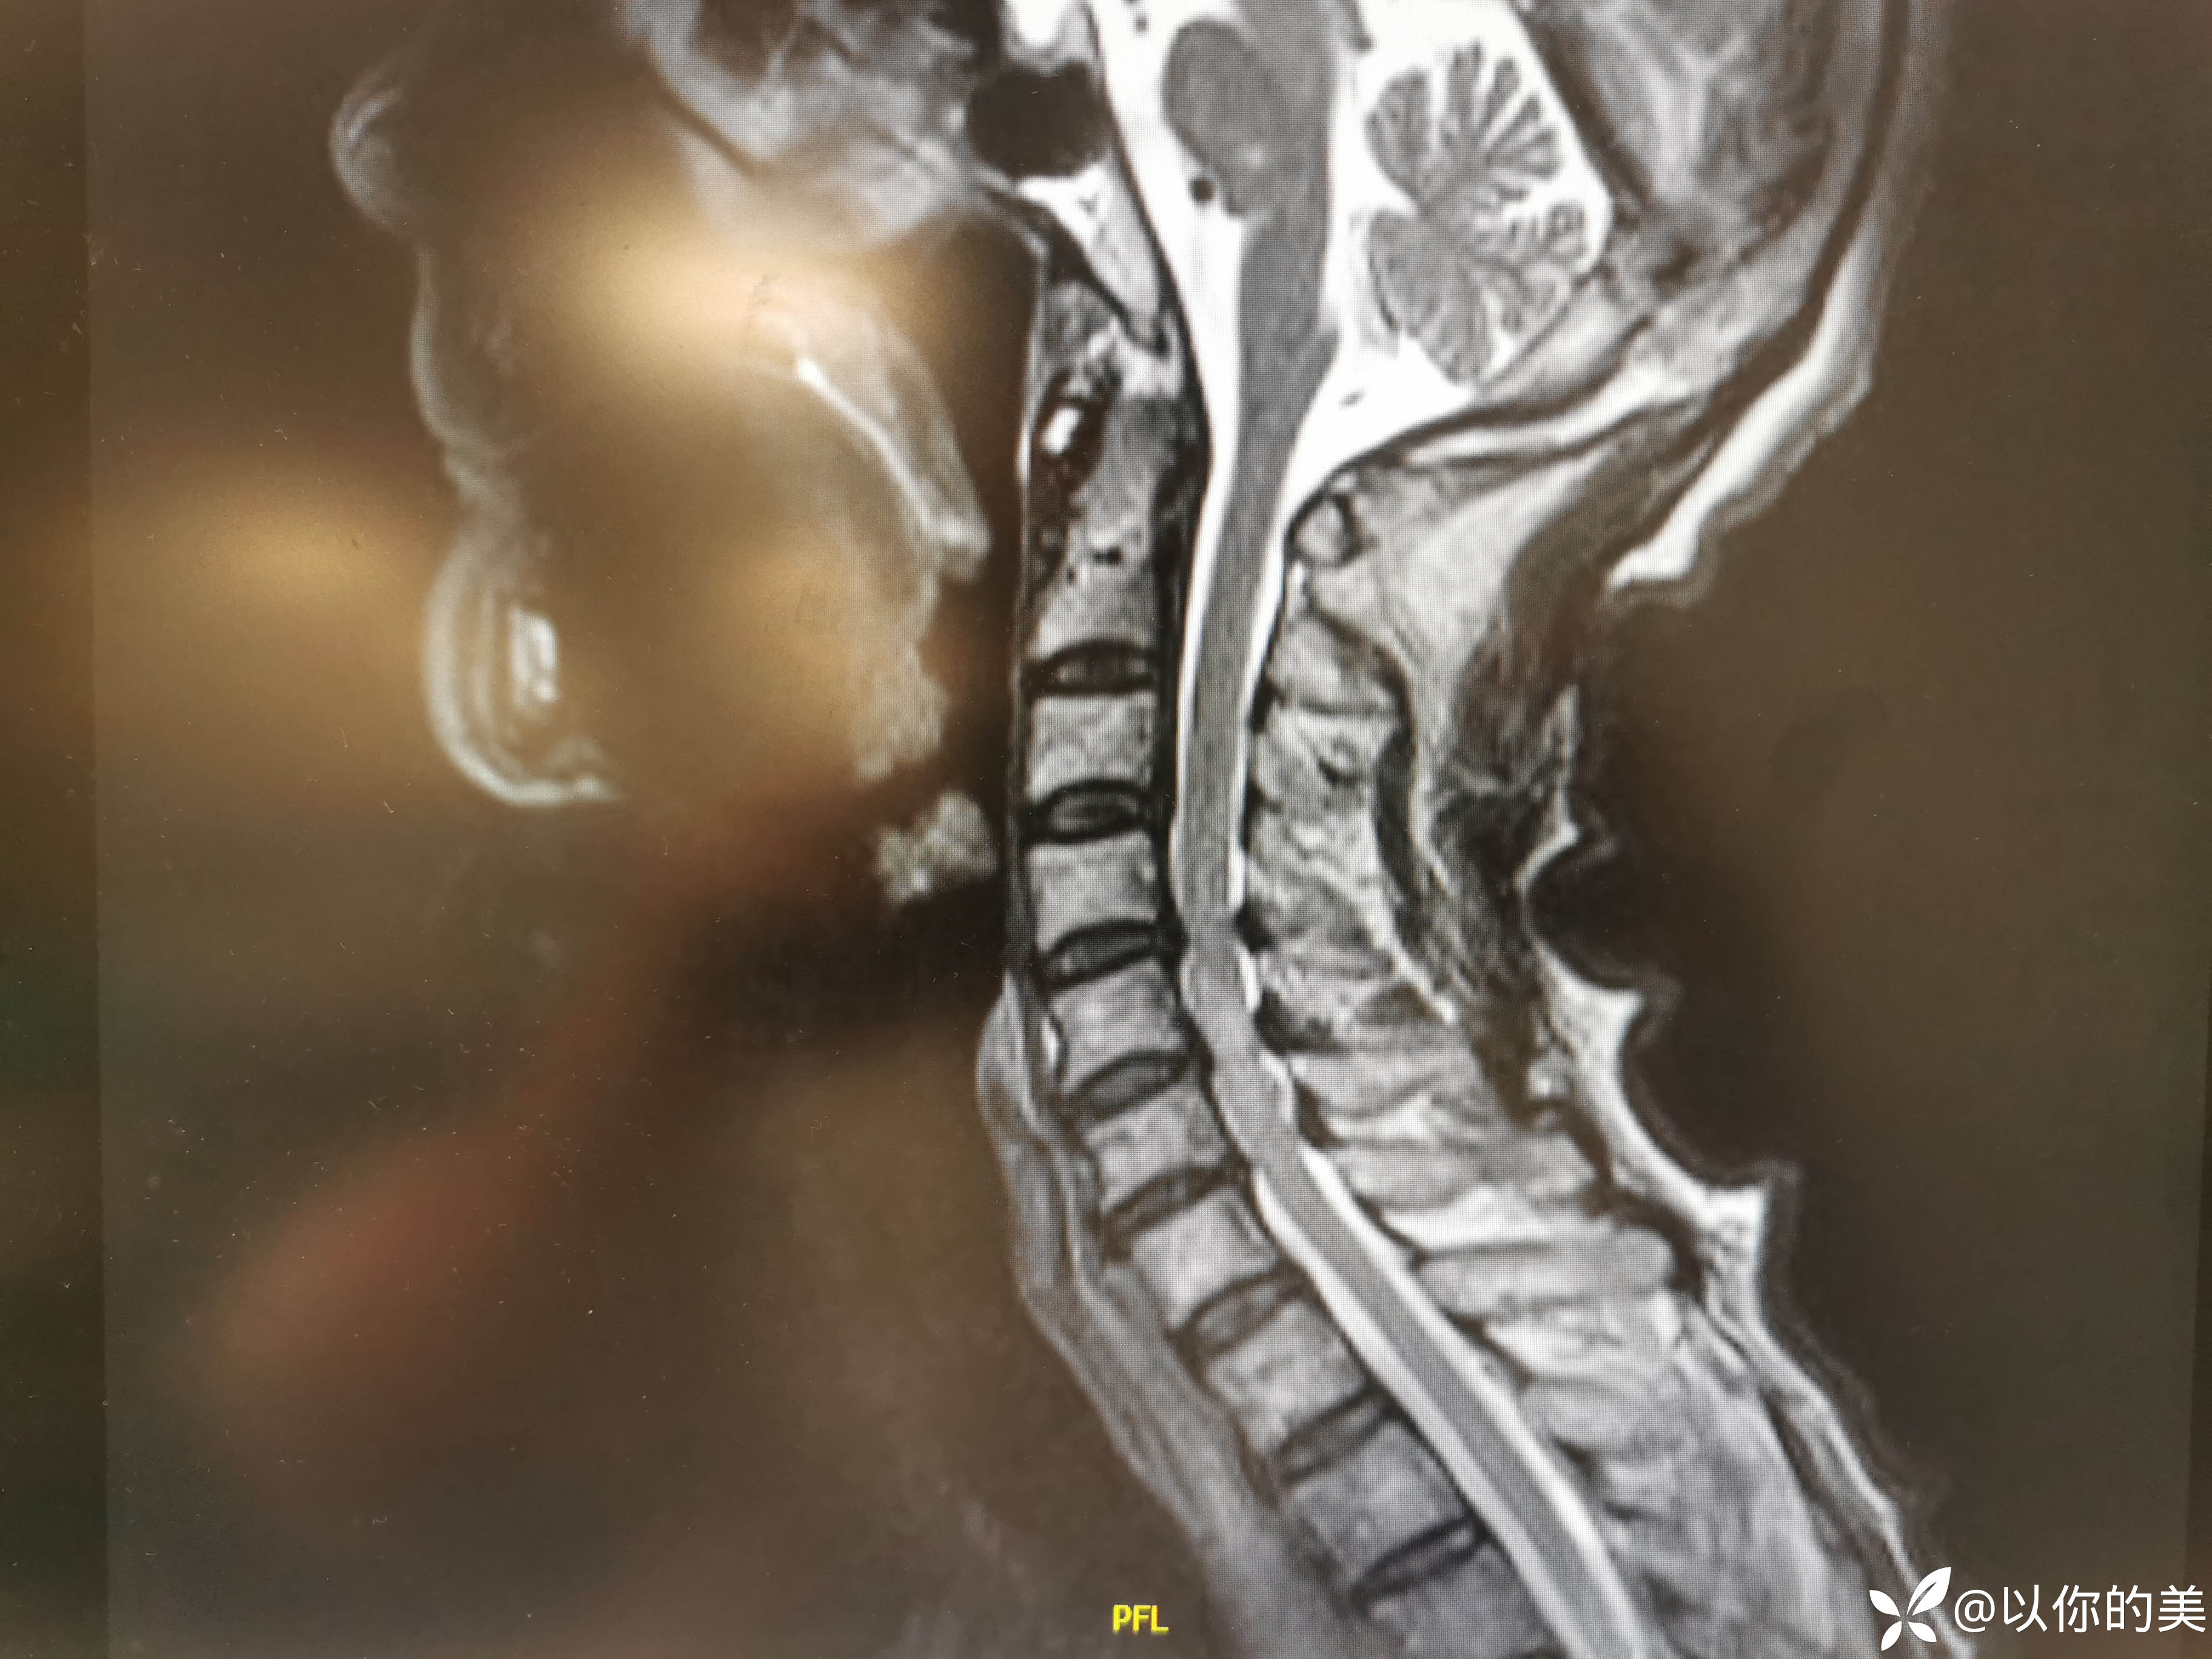

颈髓MRI:

估计患者跌倒的时候,头扭动造成的挥鞭伤。